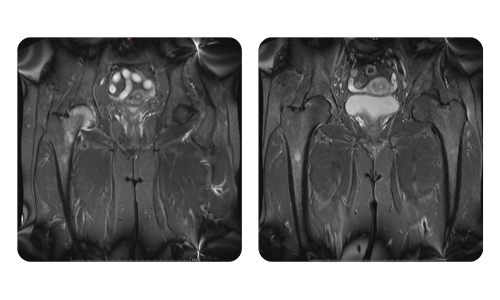

I progressi dei nostri pazienti, misurati prima e dopo la terapia iperbarica, riflettono l'efficacia e l'impatto positivo del trattamento. Scopri i risultati documentati della terapia iperbarica presso la clinica Hyperbarium Oradea, basati su valutazioni cliniche e dati oggettivi che evidenziano miglioramenti significativi in diverse condizioni.